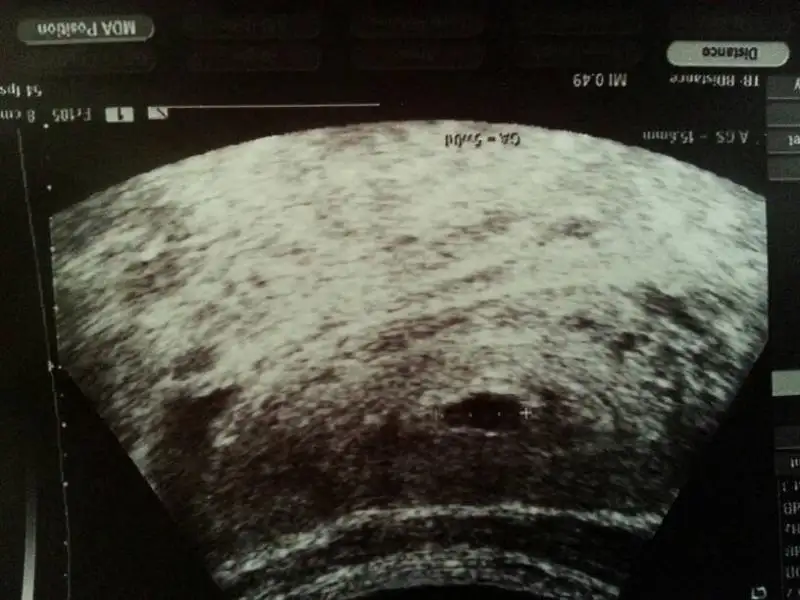

Canim bu benim kese soldaki embriyoymus

Yooo pazartesi günü ki resimilk Dr. Embriyo gördü demiştim ya 2. Dr göremedi iste bak bunlar